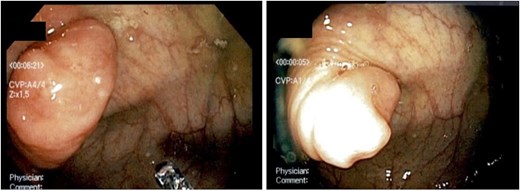

A 52-year-old female was found to have an invaginated appendix on routine screening colonoscopy (Fig. 1). She underwent subsequent computed tomography (CT) which confirmed the appendix inverting into the cecum (Fig. 2). The patient presented with no acute appendicitis or abdominal symptoms. Due to the inability to rule out appendiceal neoplasm, she was provided treatment options including surveillance and surgical removal. The patient elected to have a robotic assisted appendectomy with possible ileocecal resection depending on severity of disease. Her medical history was significant for prior cesarean section, which was evident during the robotic procedure as the uterus was adhered to the lower abdominal wall. There was no visible appendix in the right iliac fossa during inspection, but tissue could be palpated within the distal cecum. During the procedure, it was determined that the ileocecal resection was not necessary. Instead, a partial cecectomy with appendectomy was performed to spare the ileocecal valve as it was not involved. Resected margins were 3.5 × 2.7 × 0.3 cm with the inverted appendix measuring 1.8 × 1.0 cm. The operation was performed without complications, and the patient was able to be discharged later that day. The postoperative period was without complications.

Abdominal CT. An appendiceal cecal intussusception is present (arrows) with the distally located appendix invaginating into the proximally located cecum. (A) Axial view. (B) Sagittal view.